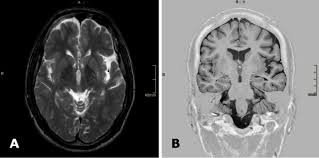

Which Genes Cause Brain Abnormalities In Phelan Mcdermid Syndrome Arm22q13